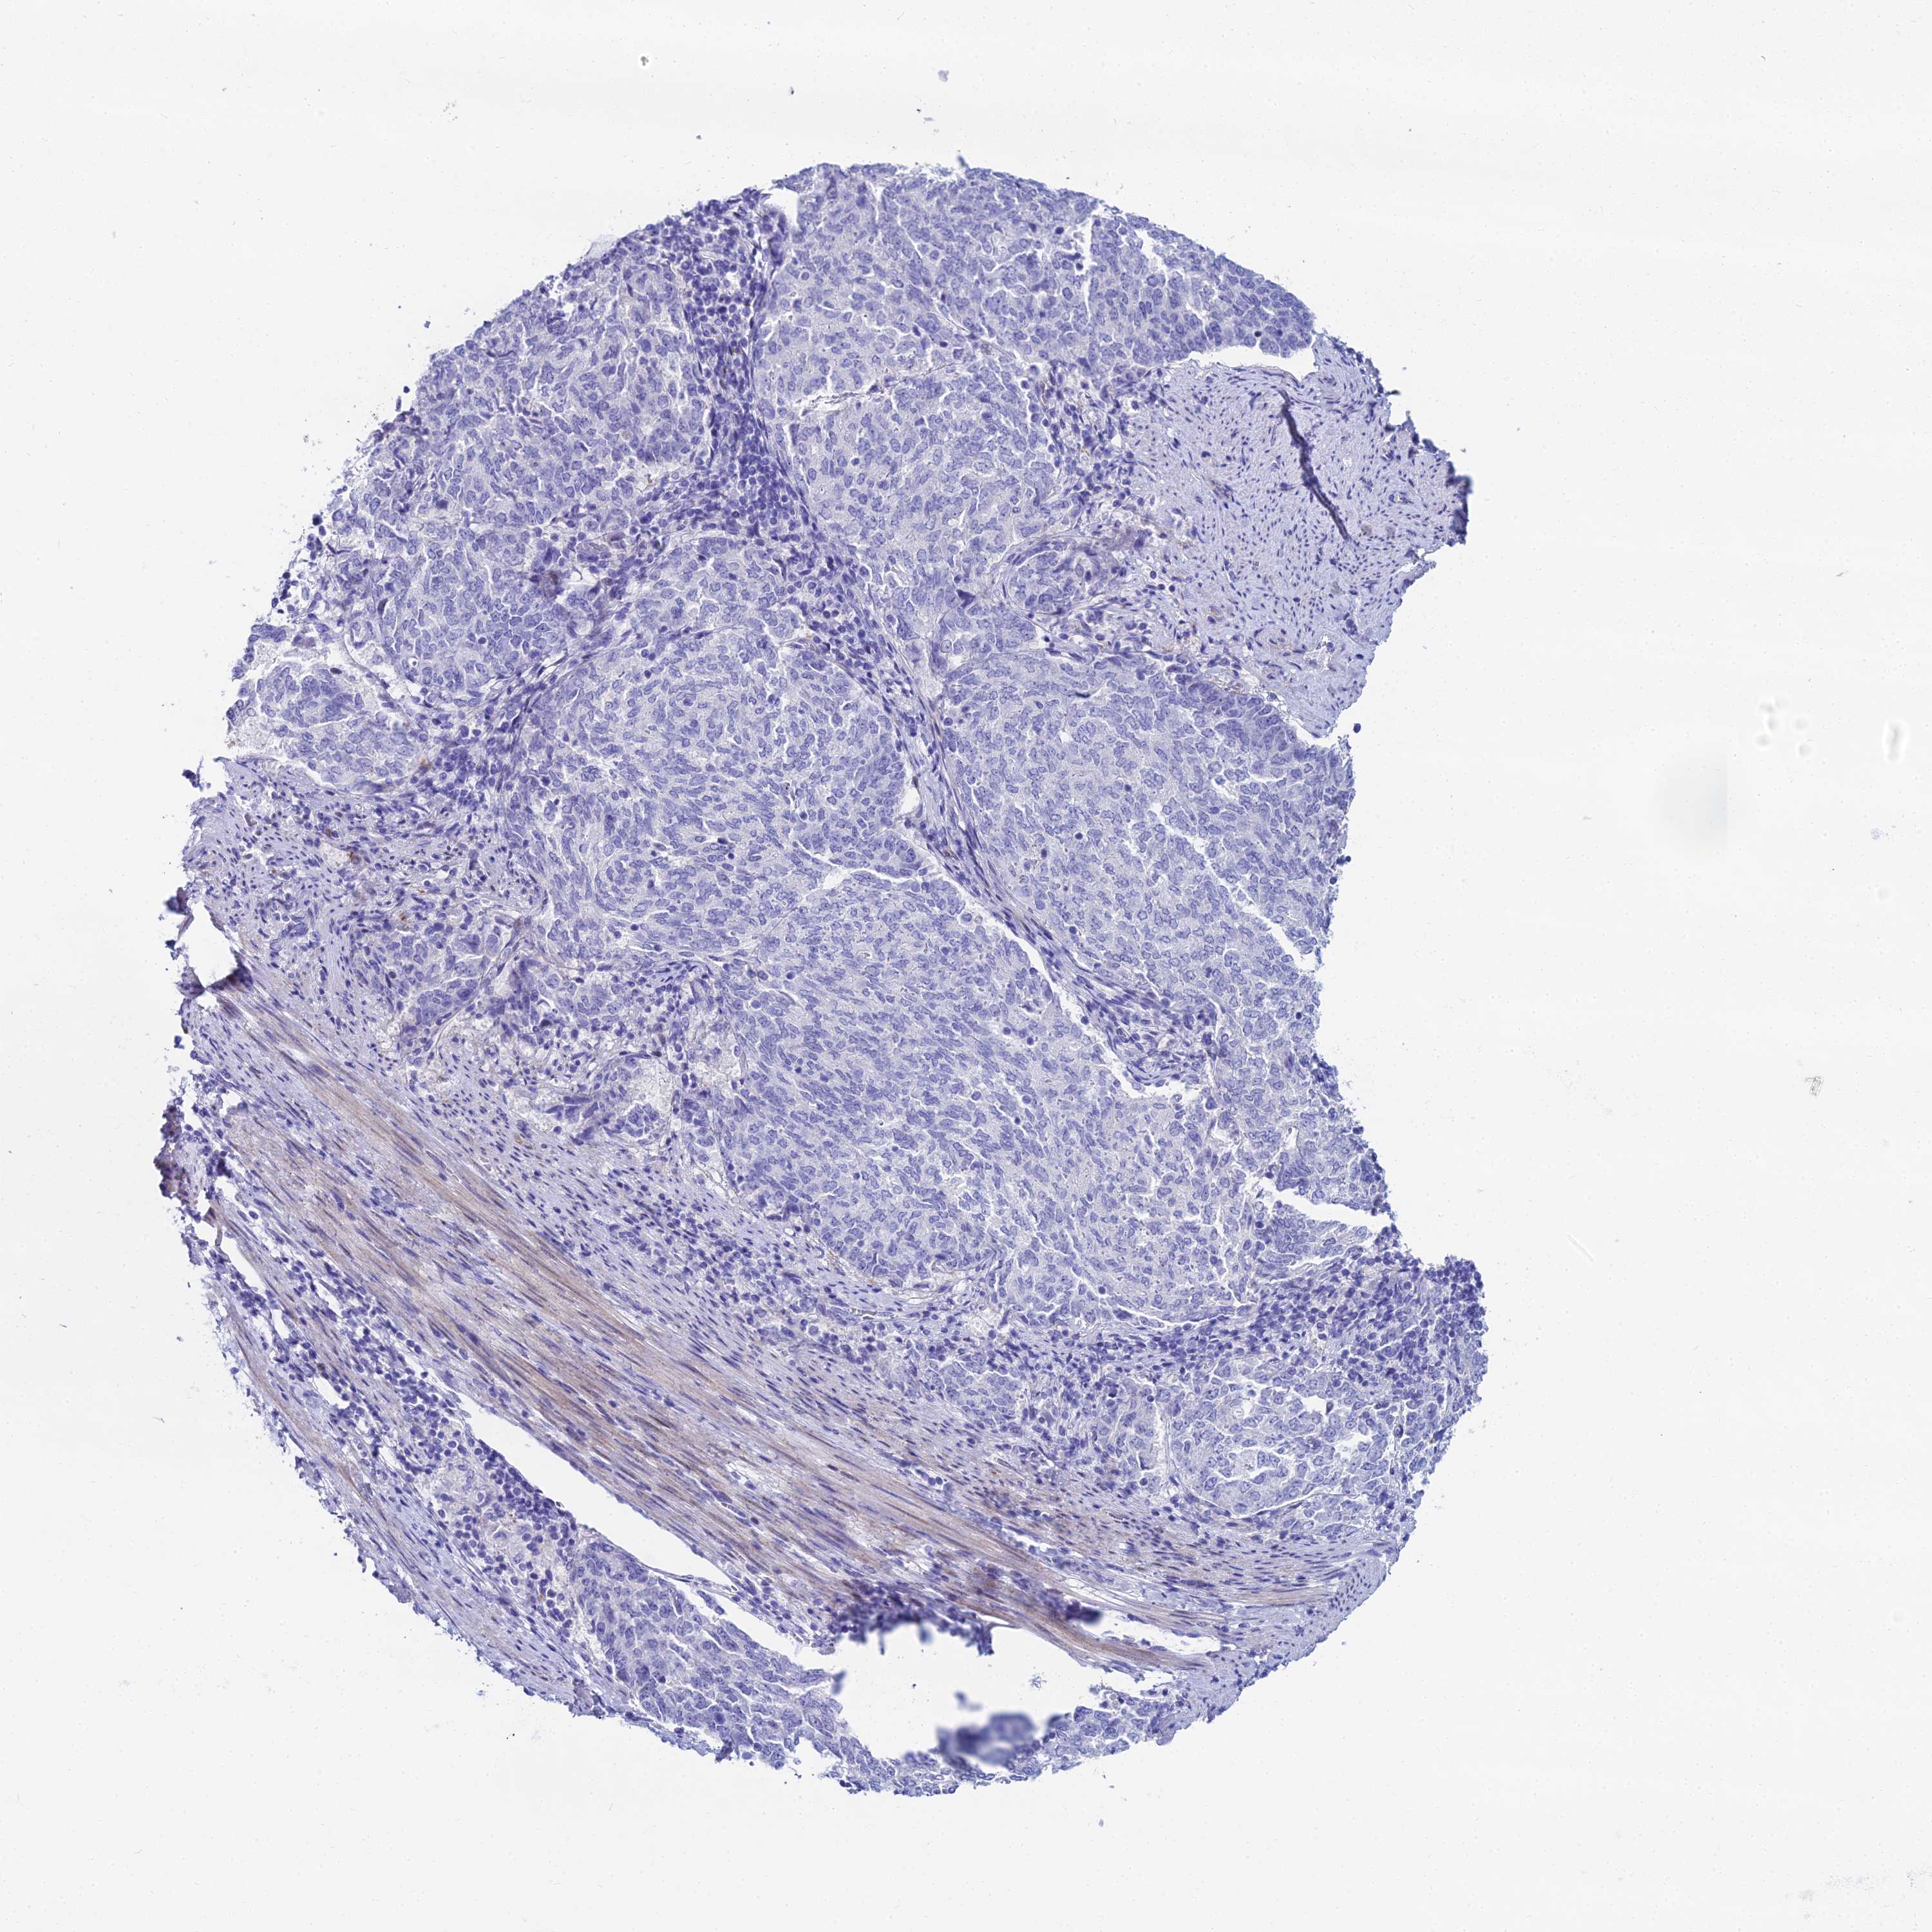

ENDOMETRIAL CANCER - Protein expressioni

A mouse-over function shows sample information and annotation data. Click on an image to view it in a full screen mode. Samples can be filtered based on level of antibody staining by selecting one or several of the following categories: high, medium, low and not detected. The assay and annotation is described here.

Note that samples used for immunohistochemistry by the Human Protein Atlas do not correspond to samples in the TCGA dataset.

Antibody stainingi

Antibody staining in the annotated cell types in the current human tissue is reported as not detected, low, medium, or high, based on conventional immunohistochemistry profiling in selected tissues. This score is based on the combination of the staining intensity and fraction of stained cells.

Each image is clickable and will lead to virtual microscopy that enables deeper exploration of all samples and also displays staining intensity scores, fraction scores and subcellular localization as well as patient and tissue information for each sample.

Antibody HPA043285

Antibody HPA052504

Staining

High

Medium

Low

Not detected

Intensity

Strong

Moderate

Weak

Negative

Quantity

>75%

75%-25%

<25%

None

Location

Nuclear

Cytoplasmic/membranous

Cytoplasmic/membranous,nuclear

Adenocarcinoma, NOS

Adenocarcinoma, metastatic, NOS

Carcinoma, NOS